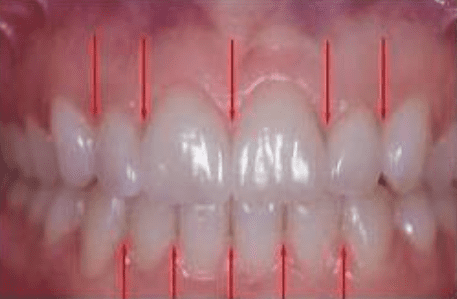

Interdental Papilla: Esthetic Considerations

By: Lee Ann Brady DMDTopic originally appeared on Pankey.org: Dr. Brady allowed permission for igniteDDS to share…